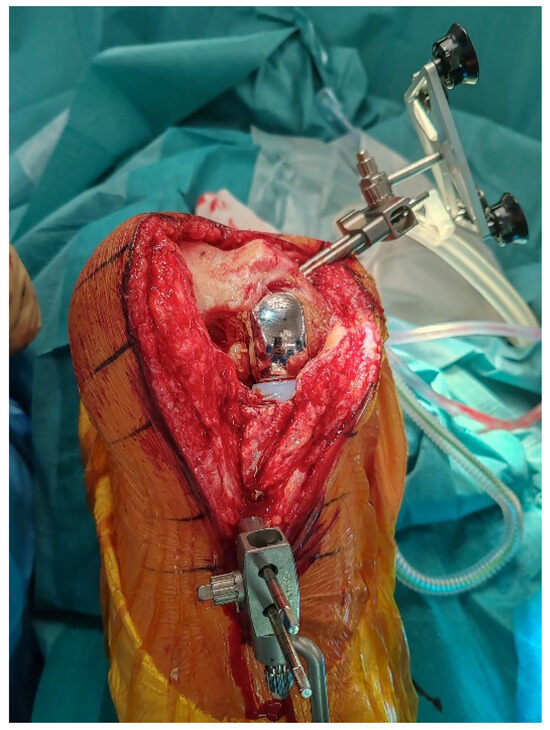

2.7. Bone Defect Management

Following explantation, any residual metaphyseal defect, most commonly located at the site of the former UKA tibial keel, is managed using autologous cancellous bone graft harvested from the femoral resections. The graft is then impacted with a tamp and mallet to recreate a stable and supportive bed for the tibial baseplate (Figure 6).

Figure 6.

Autologous cancellous bone graft harvested from femoral resections is impacted into the medial tibial defect left by the UKA keel.